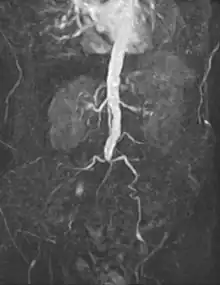

![]() Open infrarenal aortic repair model | |

Vascular surgery is a surgical subspecialty in which vascular diseases involving the arteries, veins, or lymphatic vessels, are managed by medical therapy, minimally-invasive catheter procedures and surgical reconstruction. The specialty evolved from general and cardiovascular surgery where it refined the management of just the vessels, no longer treating the heart or other organs. Modern vascular surgery includes open surgery techniques, endovascular (minimally invasive) techniques and medical management of vascular diseases - unlike the parent specialities. The vascular surgeon is trained in the diagnosis and management of diseases affecting all parts of the vascular system excluding the coronaries and intracranial vasculature. Vascular surgeons also are called to assist other physicians to carry out surgery near vessels, or to salvage vascular injuries that include hemorrhage control, dissection, occlusion or simply for safe exposure of vascular structures.[1]